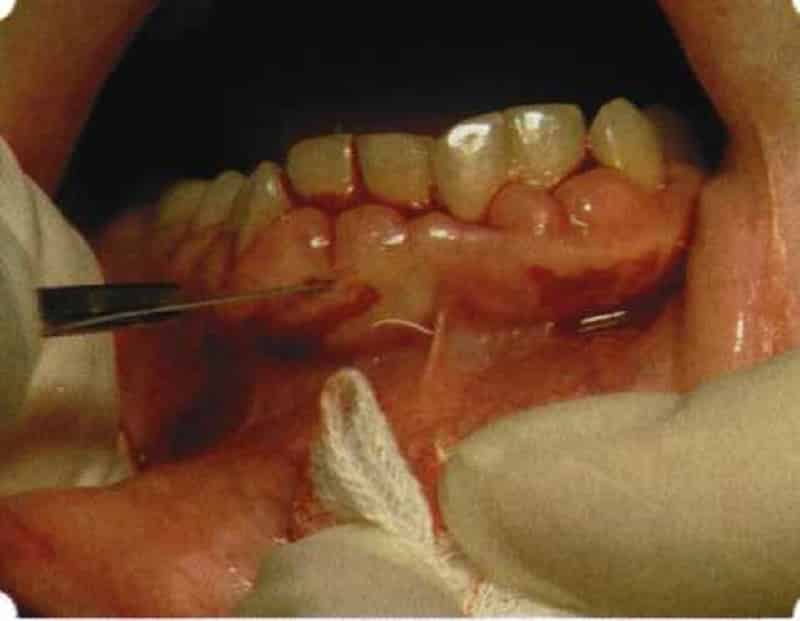

Лечение периодонтита с помощью хирургического вмешательства применяется довольно редко и, как правило, только в самых тяжелых и запущенных случаях. Этот подход включает полное или частичное удаление пораженных костных тканей, а также вскрытие области, где накапливались гнойные массы в течение болезни.

В настоящее время врачи чаще всего стремятся сохранить зуб.

При этом удалению подлежат только те его части, которые непосредственно подверглись разрушению. Оперативные методы также используются для лечения периодонтита, вызванного длительным или кратковременным воздействием определенных химических веществ. Для устранения последствий данной патологии необходимо не только удалить частицы химических соединений, но и провести обработку тканей, чтобы ликвидировать результаты негативного воздействия.